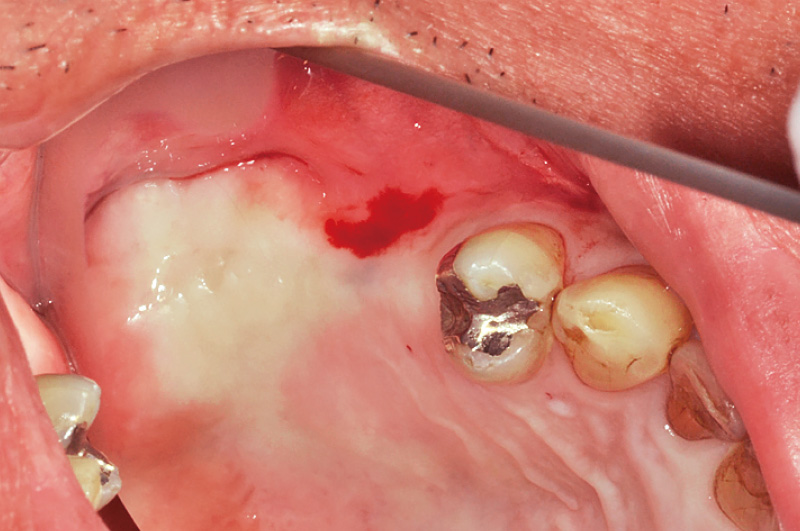

図10 症例② 2次手術前

当院にて2症例目のSPIインプラントシステムを用いた症例である。症例①と同様にインプラント埋入後、待機期間を経て2次手術前の状態を示す。 -